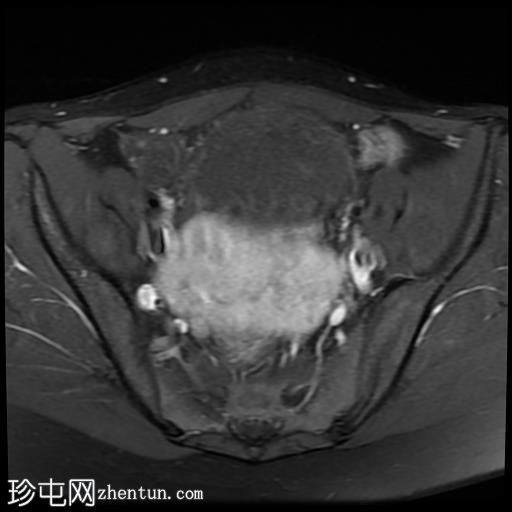

冠状位

T2加权像

5.jpg